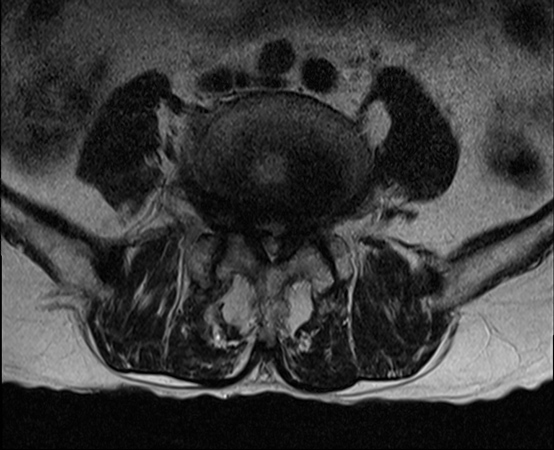

| [MRI] 요추관 협착증 |